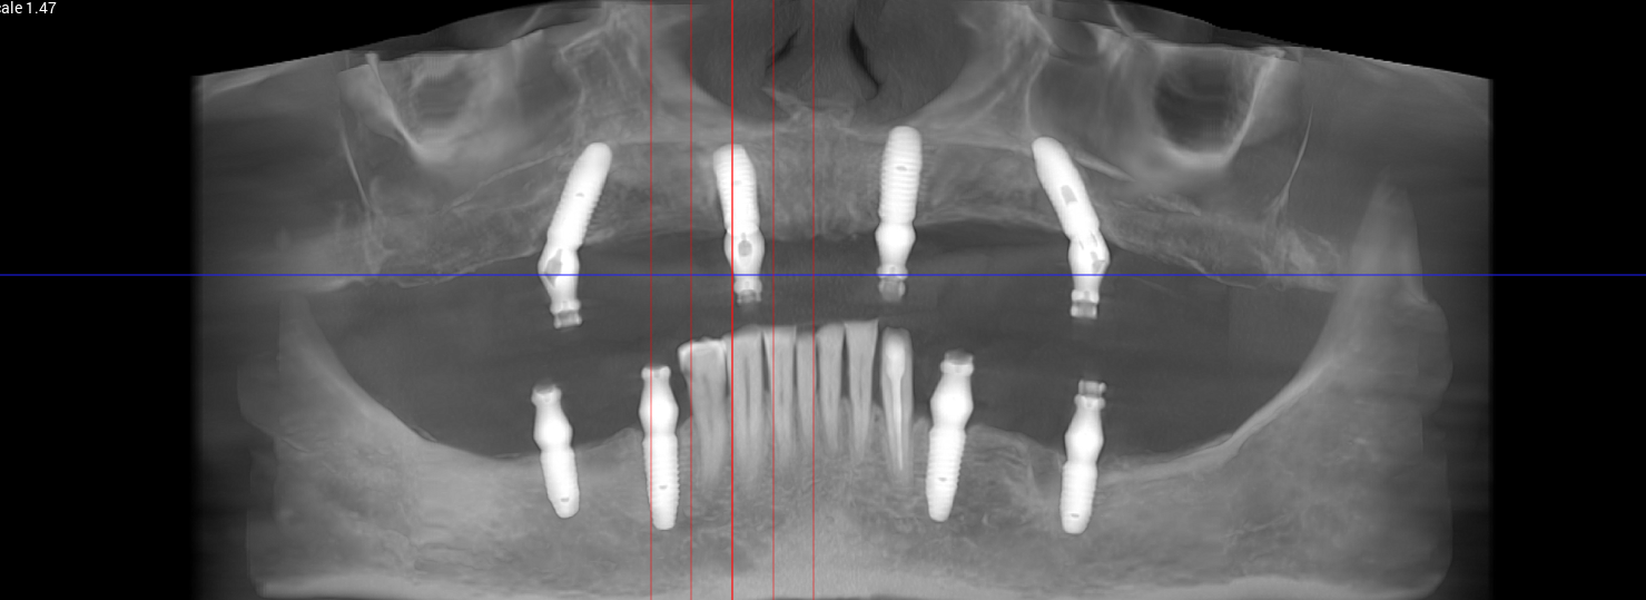

Tomografii (CBCT)

Caz 1

Caz 2

- Investigație imagistică completă, ideal CBCT (computer tomografie);